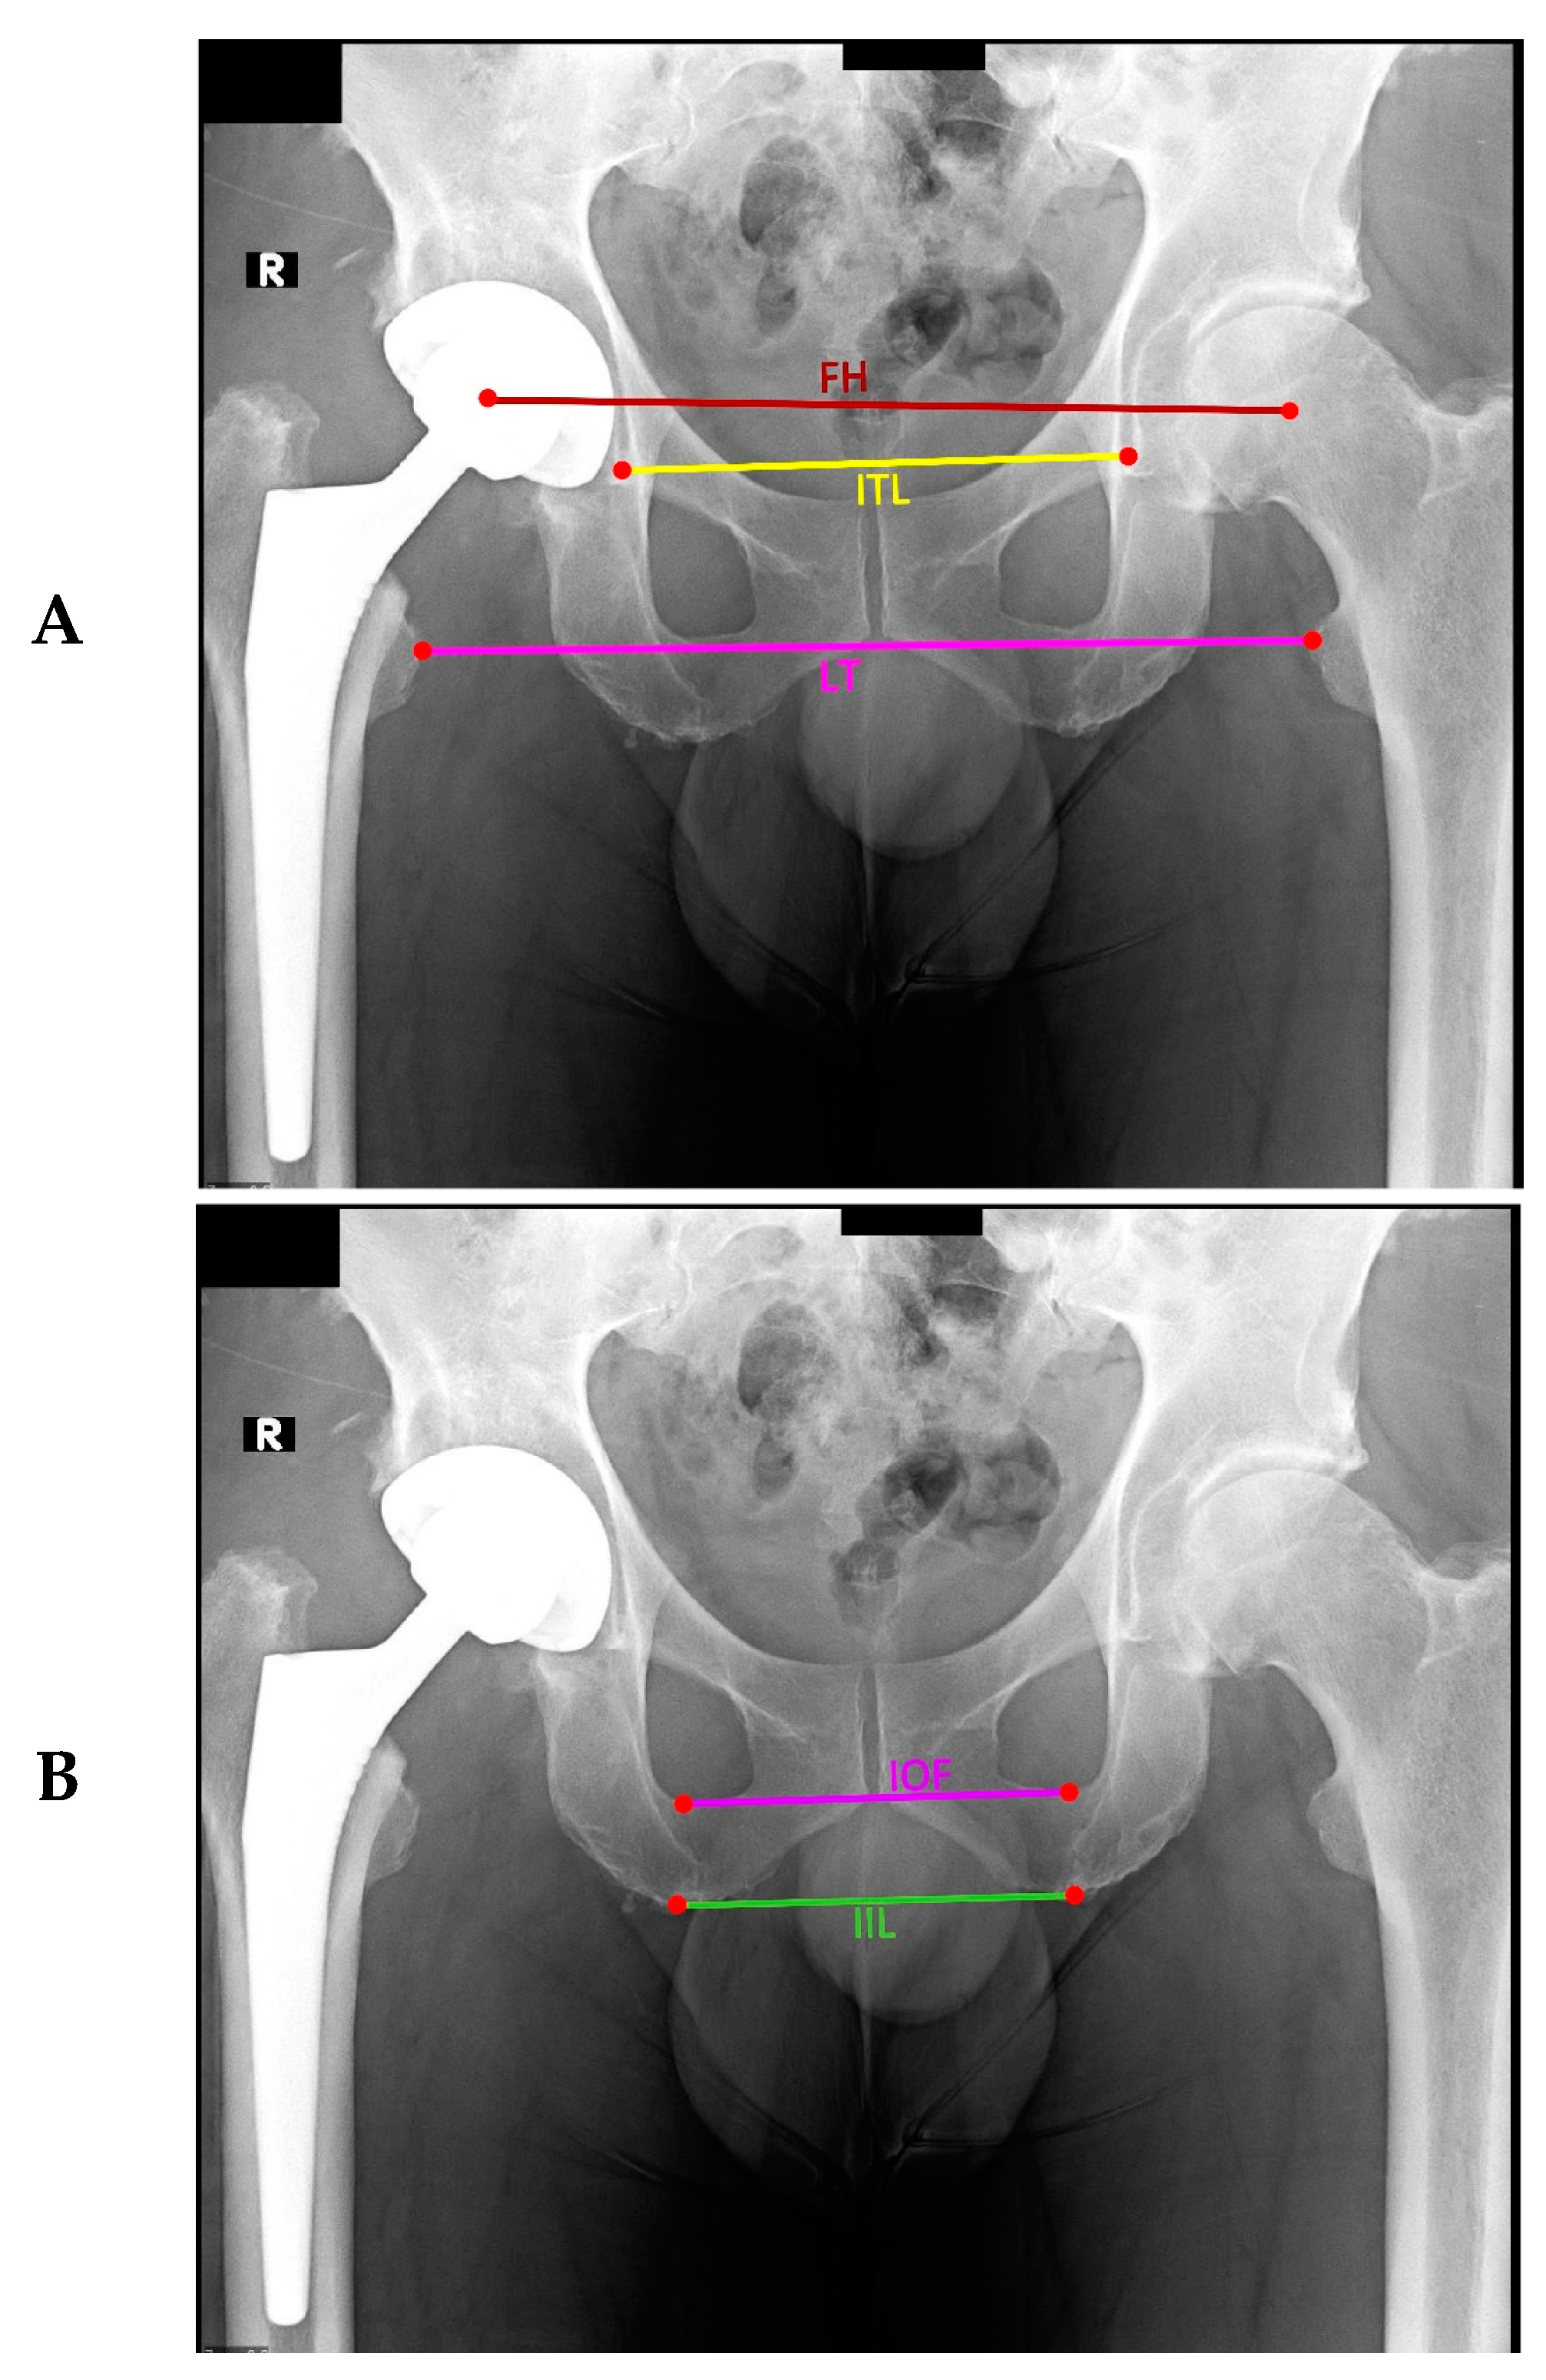

Five measurement methods were chosen for this study based on their everyday use clinically and in other studies. We used three pelvic landmarks for bisecting lines (inter-teardrop line, inter-obturator foramina, inter-ischial line) and two femoral reference points (center of femoral head, lesser trochanter, Figure 1A). Measurements analyzed were the inter-teardrop line to the center of the femoral head (hereafter referred to as ITL-FH) [42,43] the inter-teardrop line to lesser trochanter (ITL-LT) [28,44,45], the inter-ischial line to the femoral head (IIL-FH) [46] the inter-ischial line to lesser trochanter (IIL-LT) [36,47,48], and inter-obturator foramina to lesser trochanter (IOF-LT) [38,49,50]. We measured LLD on postoperative AP pelvic radiographs using these five methods, each with its landmarks (Figure 1A–C). For prosthetic leg cases, femoral head centers were evaluated using the circle theorem [51]. Healthy femoral heads were reviewed using the Mose template method [52,53] (Figure 1A).

Figure 1. Measurements of LLD are detailed in Landmarks as denoted in Figure (A) by letters A–J (A), methods referenced to the femoral head (B), and methods referenced to the lesser trochanter (C).

Figure 4. Measurements of LLD using trigonometric methods in which LLD is calculated as the product of the distance between the landmarks (the length of the connecting line) and the sine of the angle formed by the connecting line with the horizontal line. In (A) are illustrated the lines of Ischial teardrops (ITL), lesser trochanters (LT), and femoral heads (FH), while in (B) are shown the inter-ischial line (IIL) and inter-obturator foramen (IOF).